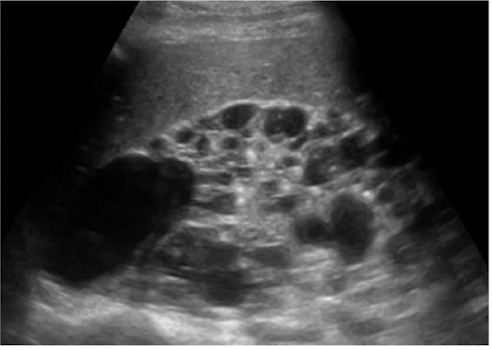

What is this and what type of scan

Polycystic kidney disease, US